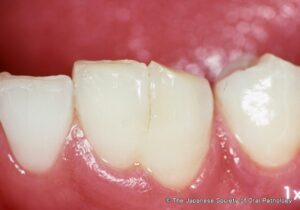

出典:口腔病理基本画像アトラス

癒合歯とは、本来であれば別々に生えてくるはずの2本の歯が、象牙質でくっついた状態で生えて1本に見える状態のことです。癒合歯は乳歯で1~5%、永久歯では0.2~0.3%で発生すると言われています。

ただし、1本の歯だけほかの歯よりも大きかったり、歯に溝が入っていたりと見た目が不自然であるため、ご家庭でも簡単に判断できます。

歯の大きさや本数が左右で異なる場合は、癒合歯の可能性が高いです。